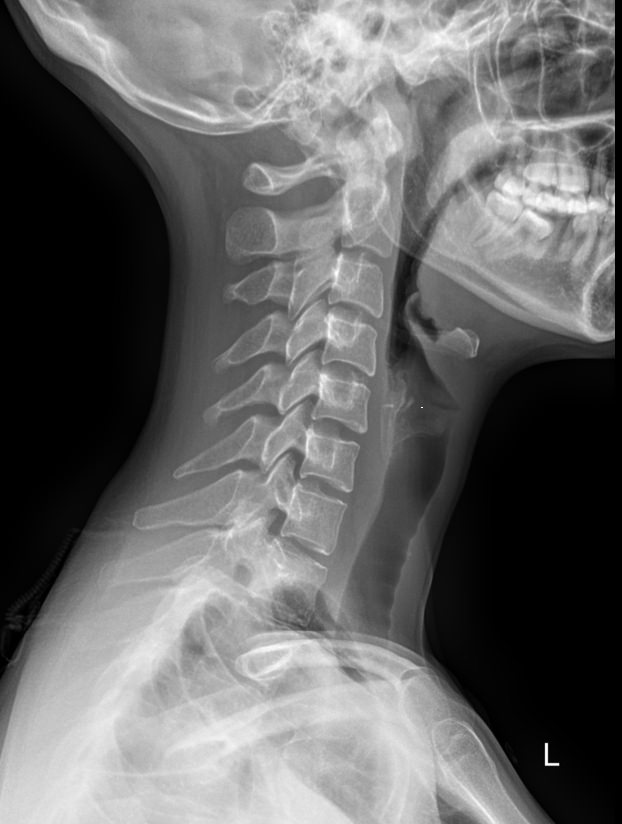

Шейный отдел позвоночника состоит из 7 небольших позвонков, в отростках которых есть отверстия для питающих голову сосудов. Этот участок позвоночного столба наиболее мобилен, однако у здорового человека движения шеи не выходят за рамки естественных. И только в случае хронических патологий наблюдается гипермобильность или, наоборот, уменьшение объема движений.

Как и другие кости, шейные позвонки отлично визуализируются с помощью рентгена. На снимках отчетливо видны признаки острых и хронических патологий, а часть врожденных аномалий обнаруживается случайно именно на рентгенограммах. В снимок попадают средние и нижние шейные, а также 2-3 верхних грудных позвонка. Для исследования двух верхних позвонков требуется специальная  проекция ― «через открытый рот».

На рентгенограмме будут видны следующие патологические изменения:

• Изменение формы тел и отростков позвонков;

• Изменение костной ткани;

• Сужение межпозвоночных пространств;

• Смещение позвонков;

• Сглаживание физиологического лордоза;

• Перелом;

• Новообразования.